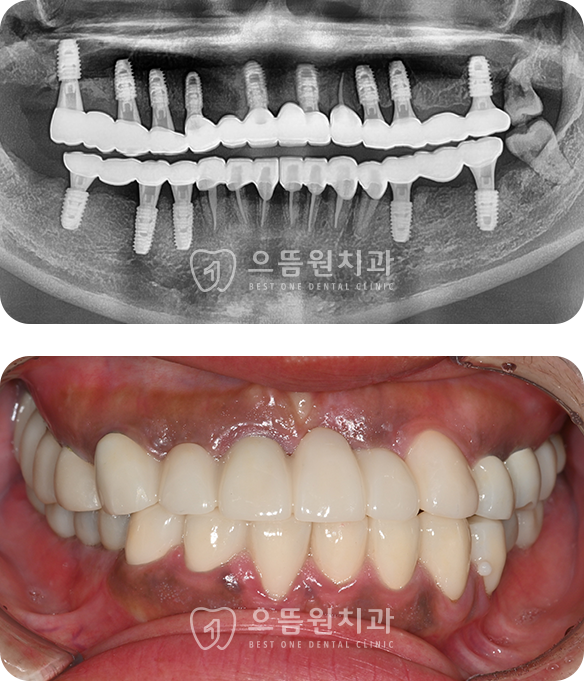

CASE 04

37세 / 여

상악 전체 임플란트, 하악 구치부 임플란트

다발성 우식과 치석으로 인해 전체 치아가 망가지셨던 환자분

젊은 나이임에도 불구하고 일상 생활과 식사가 어려우셨습니다.

교합이 무너져있으며 치아우식과 치주질환이 심하였고 뼈도 약한 상태였으나

적절한 치주치료와 근관치료, 뼈이식과 상악동 거상술을 동반하여

임플란트와 보철치료를 완료하였습니다.

치료기간 : 2024.07.08 ~ 2025.05.12

BEFORE

AFTER